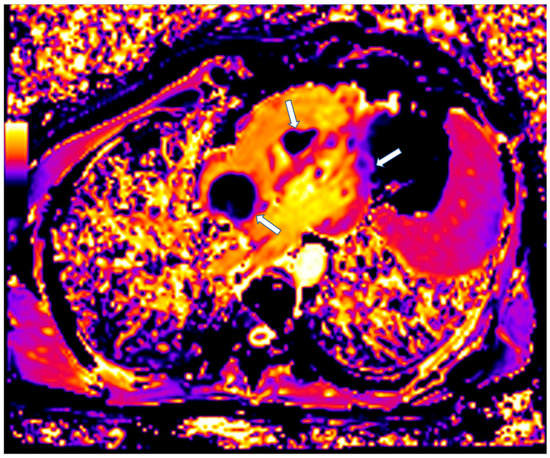

Figure 3.

Short axis LGE image showing diffuse subendocardial fibrosis (arrows) in a patient with Churg–Strauss vasculitis.